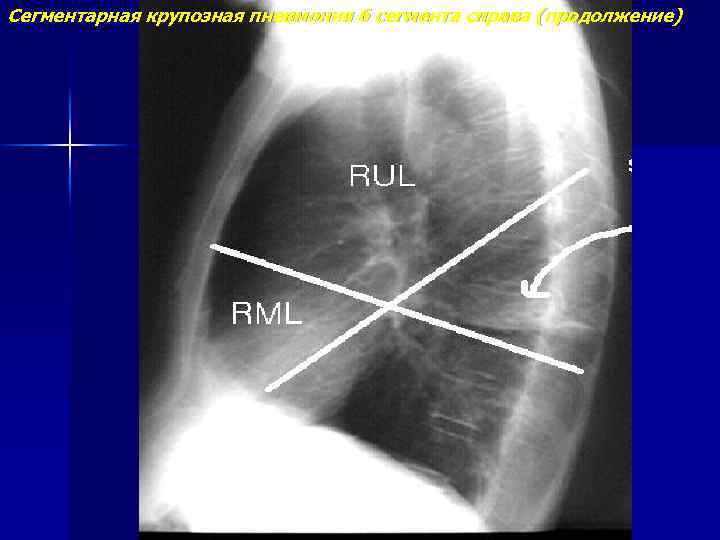

Сегментарная крупозная пневмония 6 сегмента справа

Сегментарная крупозная пневмония 6 сегмента справа (продолжение)